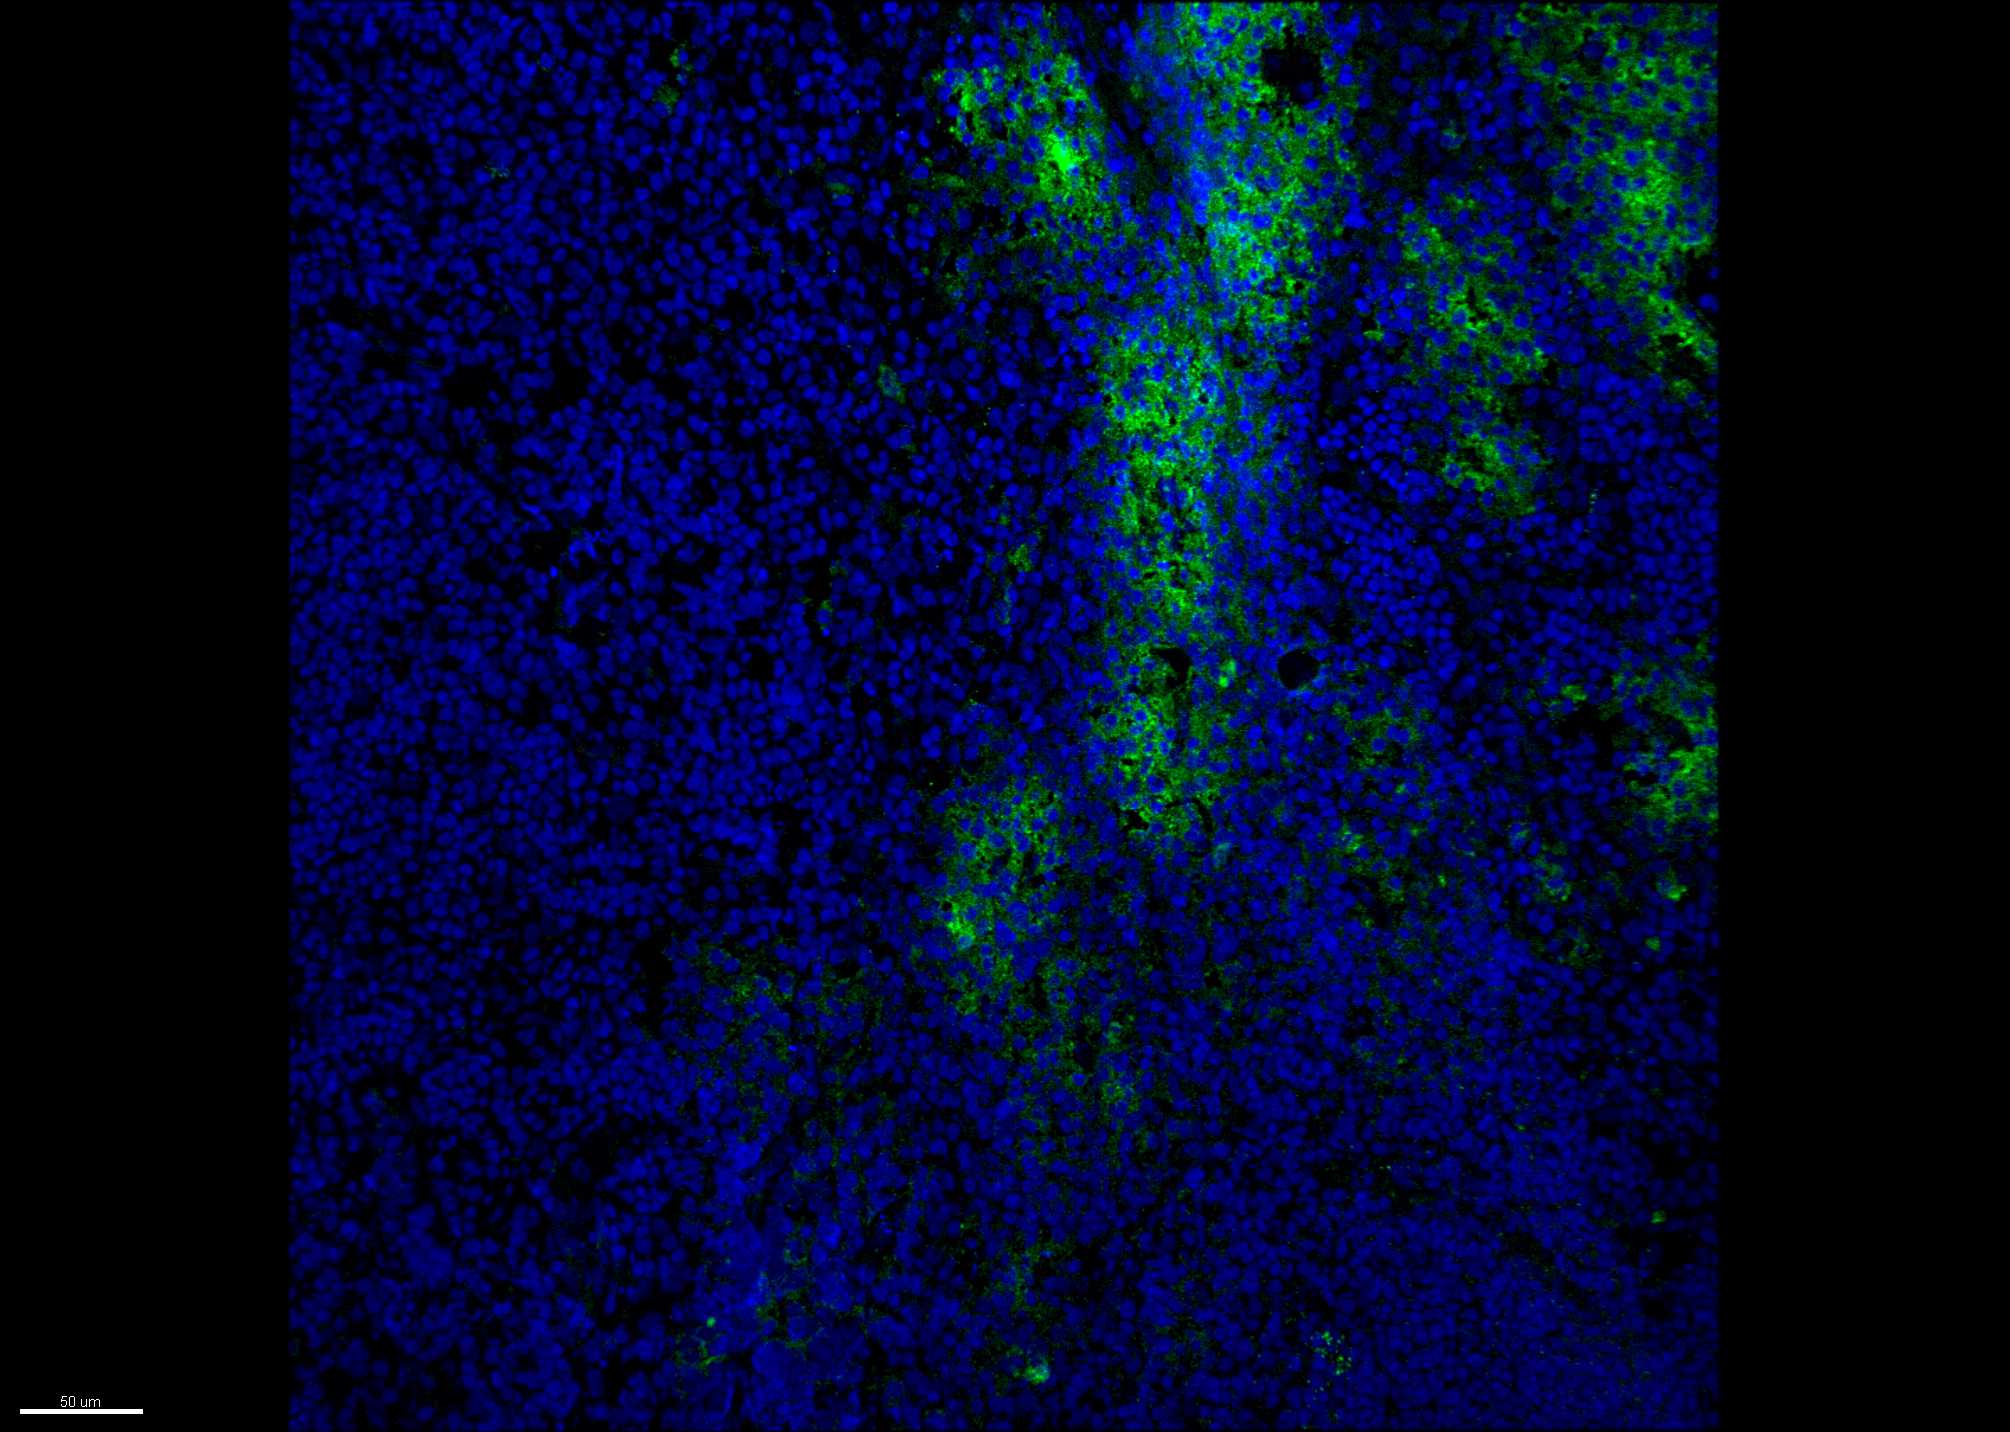

Other IL-4R alpha FAB230G

Enlarge

Immunofluorescence-frozen Human 07/25/2019

ApplicationOther

Sample TestedHuman Tonsil tissue

SpeciesHuman

Comments

Commentsacetone fixation